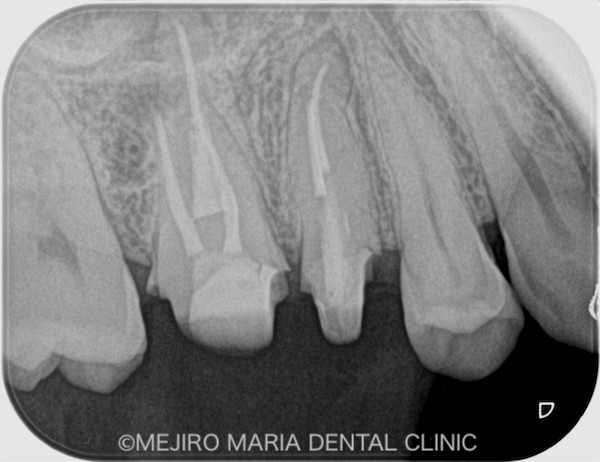

右上6番の歯に確認できたフィステル(瘻孔)は、2回目の根管治療の際にはすでに消失していました。患者様のご希望により、すでに根管治療がされている手前側の歯(右上5番)も、根管治療をやり直すこととなりました。

治療後の様子

赤丸は病変が消失したところ

術後3ヶ月の経過は良好だったため、最終補綴処置を完了し、その後1年間、経過を確認しました。その結果、右上6番の歯に確認できていた病変も消失し、現時点は予後良好と判断しています。